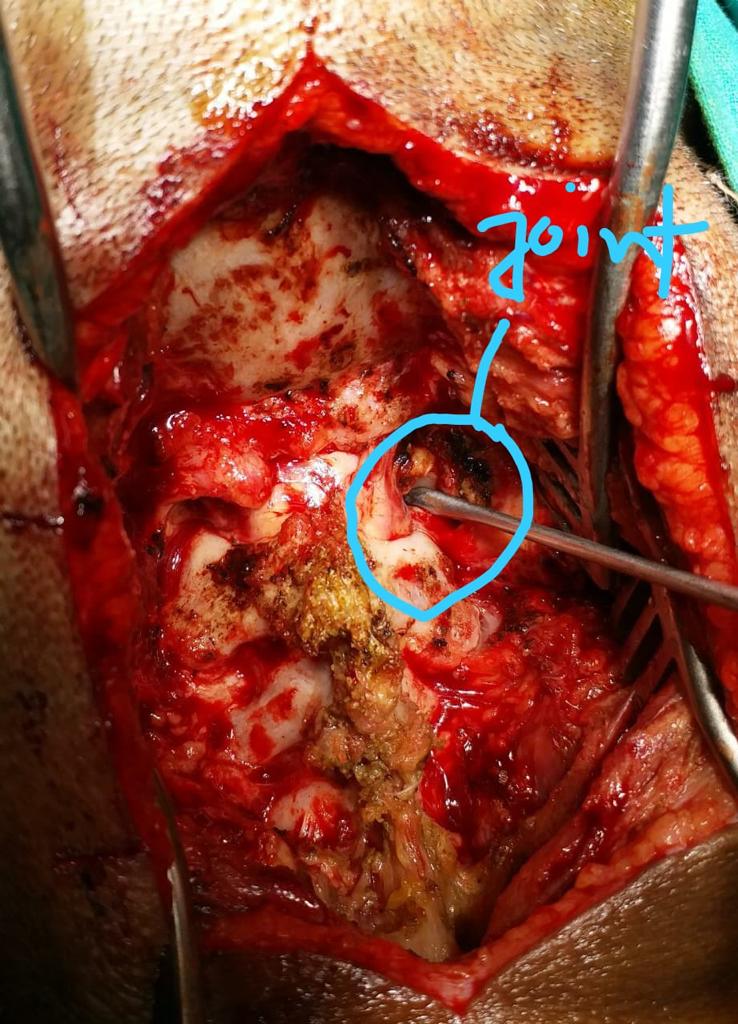

Cases